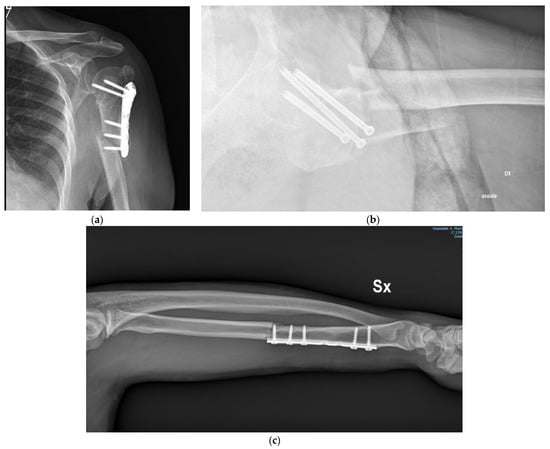

- Question about the BONE—In which bone is the fracture? Number 1–15;

- Question about the HARDWARE—What is the hardware and what is its length? A–ε and I–VI;

- Question about the FRACTURE—Where is the fracture (compared to the hardware)? A–C.

- α: plate and screws;

- β: screws;

- γ: nail;

- δ: K-wires;

- ε: external fixator.